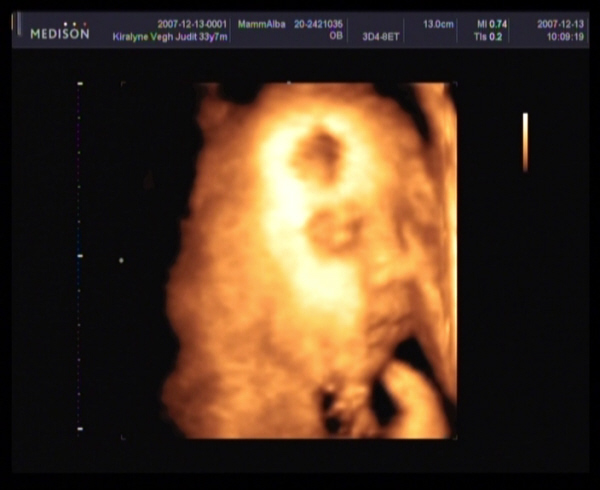

Judy,

gyere a képekkel!!!! Nagyon kíváncsi vagyok Barbikára!!!!!